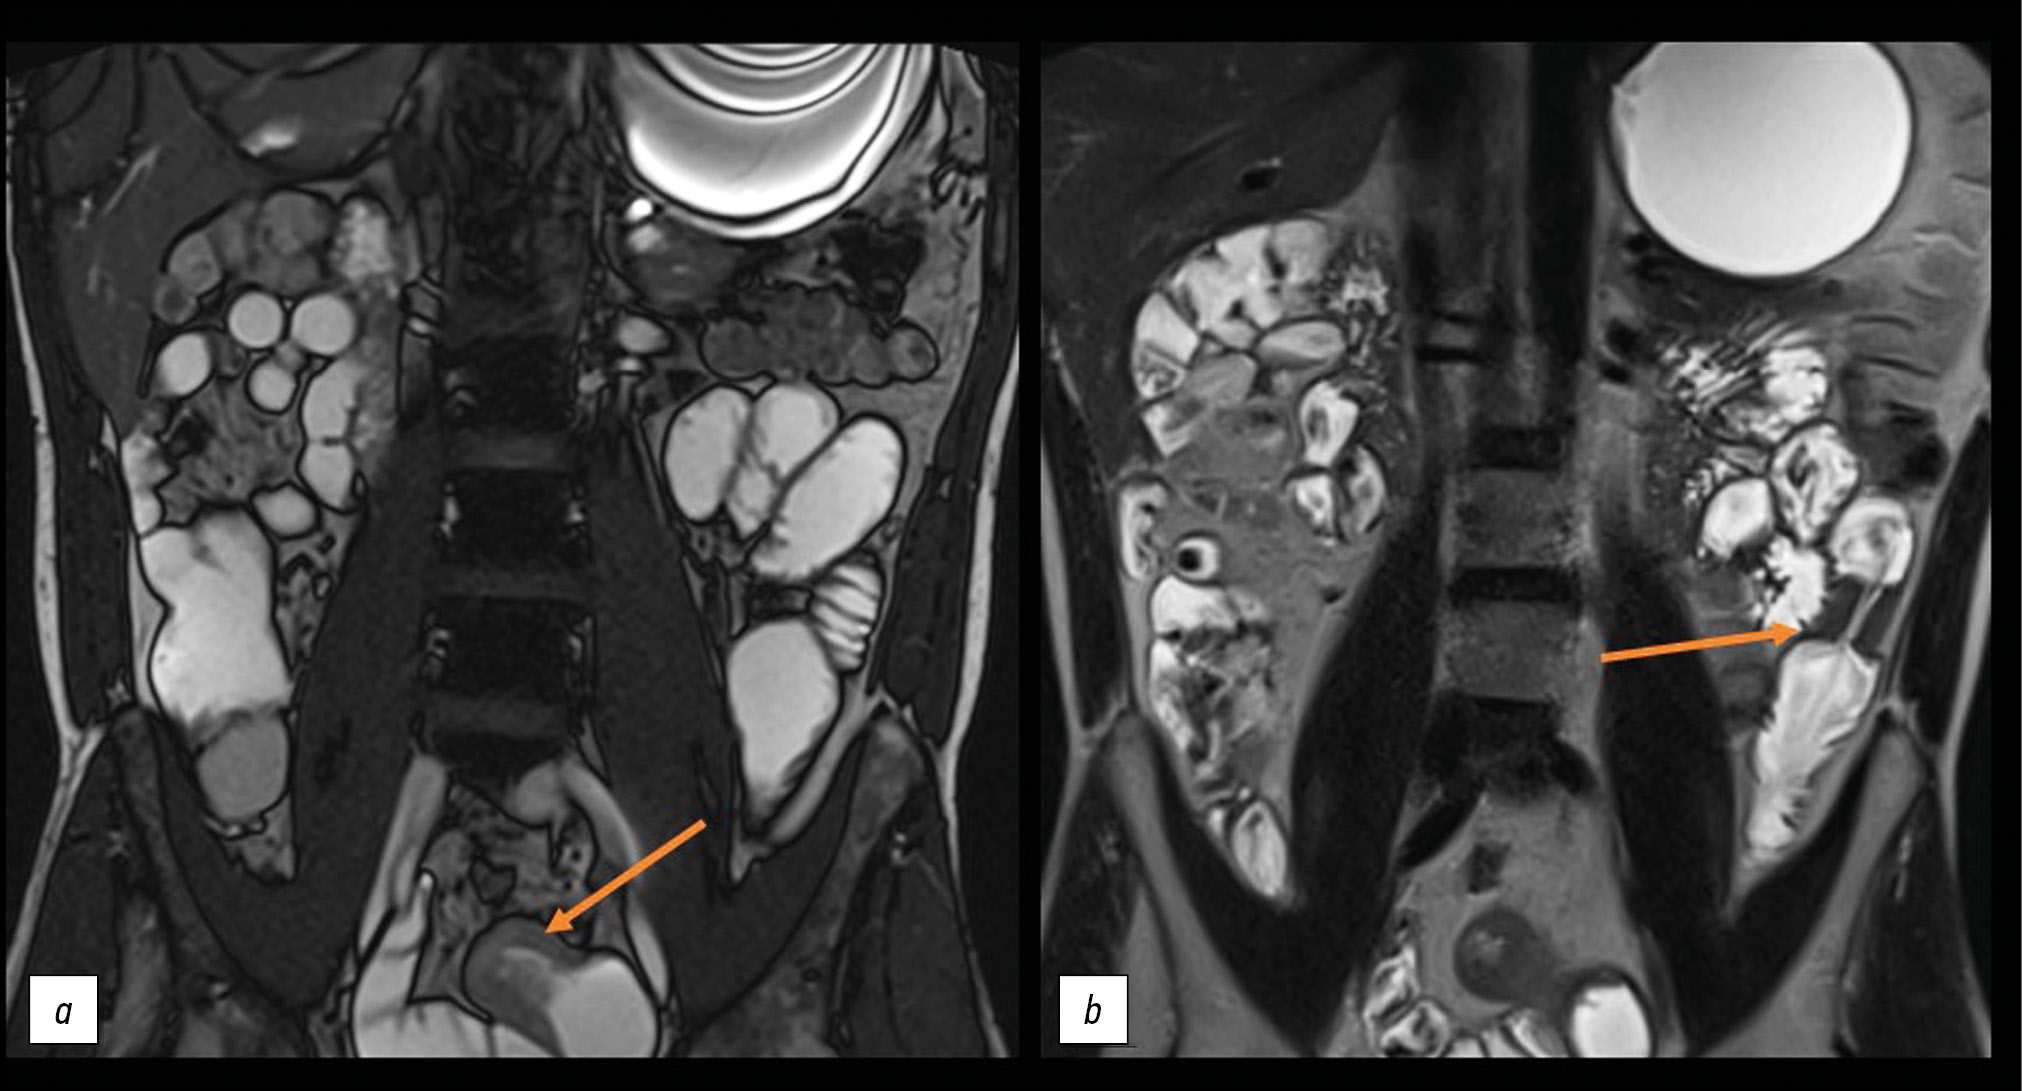

To determine the extent and volume of the lesion, MR enterography was performed after administering 1.2 L of mannitol solution orally. Four local areas of uneven wall thickening were noted in the small intestine: thickening of up to 8 mm over 25 mm with narrowing of the lumen to 5 mm, thickening of up to 12 mm over ~90 mm with narrowing of the lumen to 3 mm, thickening of up to 10 mm over 160 mm with narrowing of the lumen to 3 mm, and thickening of up to 9 mm over ~32 mm with narrowing of the lumen to 3 mm (Figs. 2 and 3). These areas of the small intestine actively accumulated the contrast agent and showed signs of limited diffusion on diffusion-weighted imaging. Because the lesions resembled those seen in intestinal tuberculosis, an immunodiagnosis of tuberculosis infection (interferon gamma release assays, T-SPOT.TB, with a negative result) and chest MSCT (with no pathology) were performed.

Fig. 3. Magnetic resonance enterography, coronal plane: the arrows show areas of thickening of the long sections of the small intestine walls.